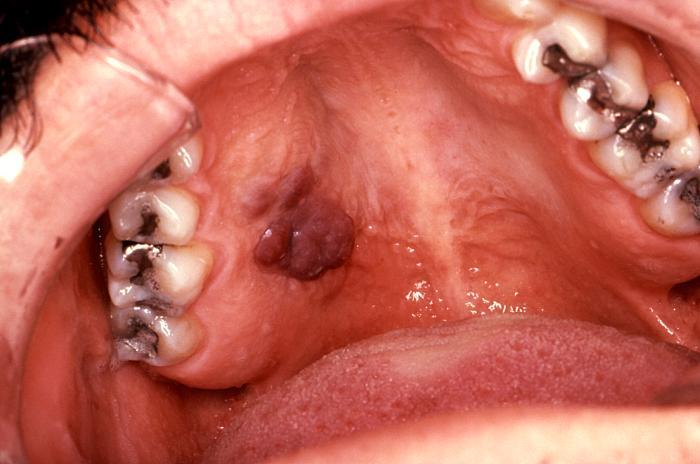

KS mucosal lesion

Intraoral KS in patient with AIDS. About 10% of patients with advanced AIDS will have mucosal lesions of KS. Lesions may be small to larger, nodular growths.

Source: CDC, S. Silverman DDS San Francisco

• HIV-associated Kaposi sarcoma (KS): typically characterized by violaceous vascular lesions on skin [Fig 1], mucous membranes [Fig 2] and/or viscera (e.g., GI tract and lungs).